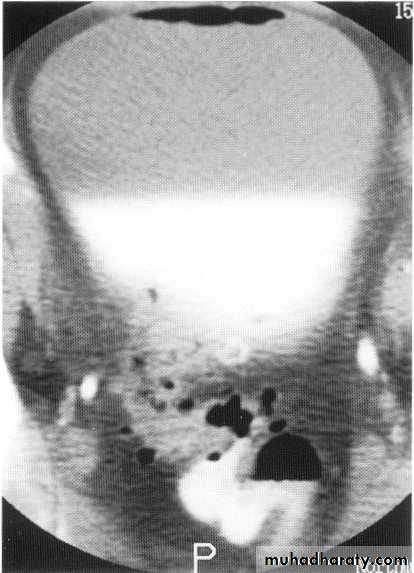

Ct scan carinal LAP